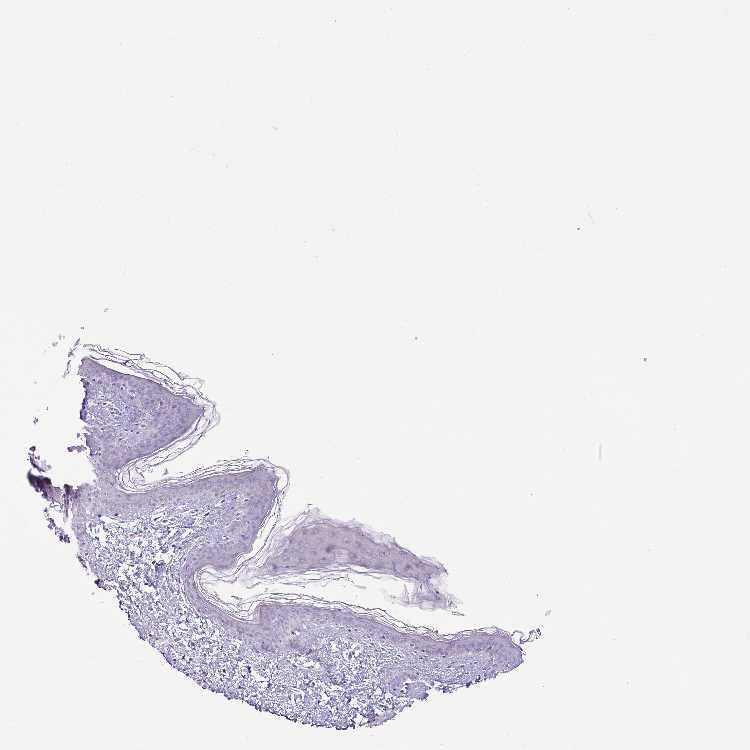

SKIN 1 - Antibody stainingi

Antibody staining in the annotated cell types in the current human tissue is reported as not detected, low, medium, or high, based on conventional immunohistochemistry profiling in selected tissues. This score is based on the combination of the staining intensity and fraction of stained cells.

Each image is clickable and will lead to virtual microscopy that enables deeper exploration of all samples and also displays staining intensity scores, fraction scores and subcellular localization as well as patient and tissue information for each sample.

Antibody HPA052843

Langerhans Not detected

Fibroblasts Not detected

Keratinocytes Not detected

Melanocytes Not detected